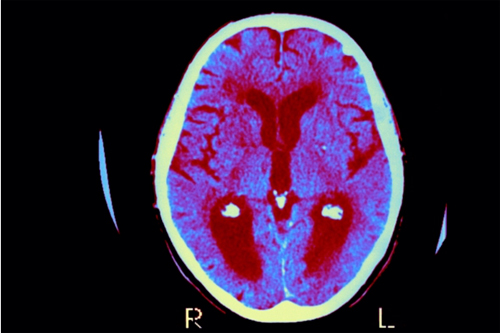

阿尔茨海默病是一种毁灭性的疾病,目前已有超过500万美国人因此丧失了认知能力和记忆功能,而科学家们一直以来都对其发病根源感到困惑不已...

人们大脑对入侵微生物的防御会导致阿尔茨海默氏症,这表明疫苗能够预防这一状况...

研究人员发表在美国人类基因遗传学杂志的研究报告表明,男性的血液样本显示Y染色体丢失发展成阿尔兹海默病的人,和那些出生就携带能促使他们以*高风险患上此病基因的人一样...